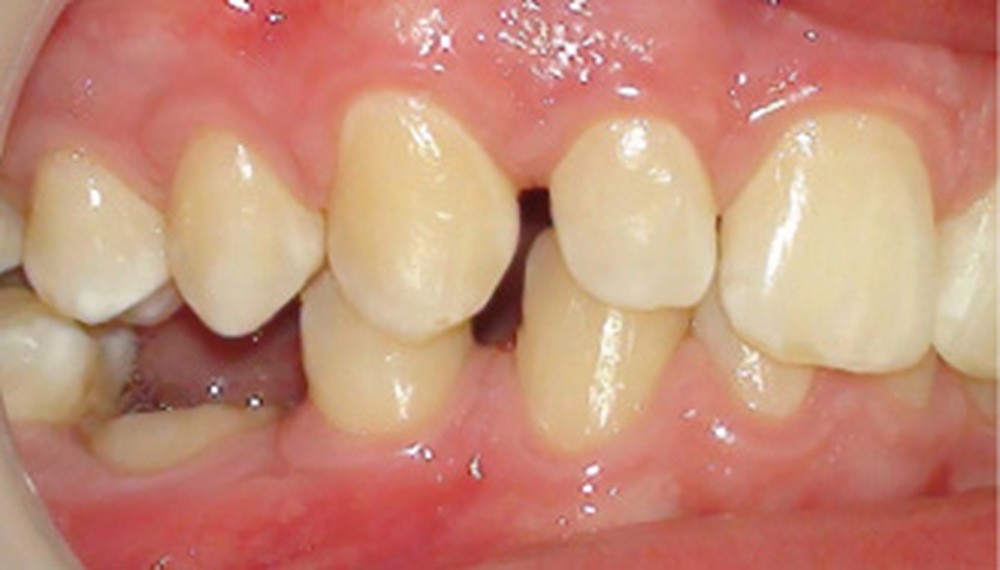

L’infraclusion de la molaire temporaire, et dans son cas extrême sa réinclusion, est le résultat d’une ankylose de la dent. Cette dent ne pourra plus suivre la croissance de l’os maxillaire ou mandibulaire et ainsi le plan d’occlusion. La molaire temporaire ne présentant pas de germe définitif sous-jacent, elle s’ankylose fréquemment à un stade plus ou moins avancé de l’individu et de la croissance des maxillaires.

D’un point de vue histologique, dans l’ankylose dento-alvéolaire, il existe une continuité de tissus durs (os-cément) avec rupture du ligament alvéolo-dentaire, précédée par une disparition locale des éléments épithéliaux de Malassez, isolants de la gaine péri-dentaire [1]. Il en résulte une résorption de la racine dont la vitesse correspond à la vitesse du remodelage osseux. Ce processus est défini comme « résorption de remplacement », l’os prenant la place du desmodonte et de la racine dans la zone ankylosée [2]. Lorsque…